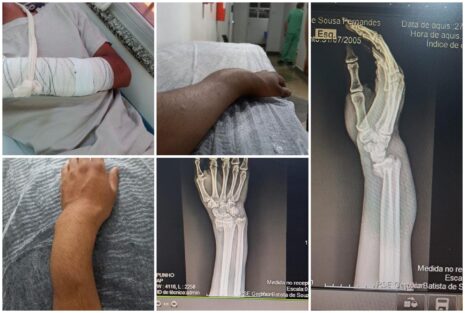

Segundo relato do jovem entregador, no último sábado, quando trabalhava fazendo entregas, ele passou próximo à antiga guarida, saída para Luziânia, quando cachorro grande entrou na frente de sua moto e o fez cair. Na queda, infelizmente, ele fraturou um dos pulsos.

Agora, o motociclista aguarda por uma cirurgia. Ele informou que além do cão em que ele colidiu, existiam outros quatro cães nas proximidades onde aconteceu o acidente.